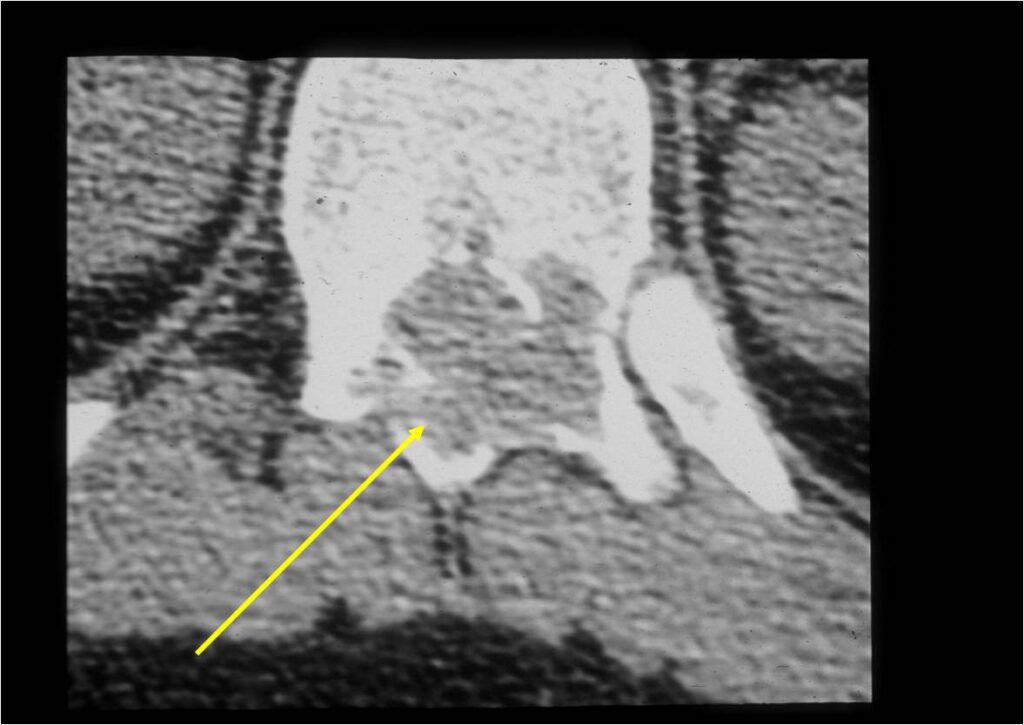

CT Scan:

- More useful for detecting mineralization and evaluating extent of bone destruction than plain X-ray